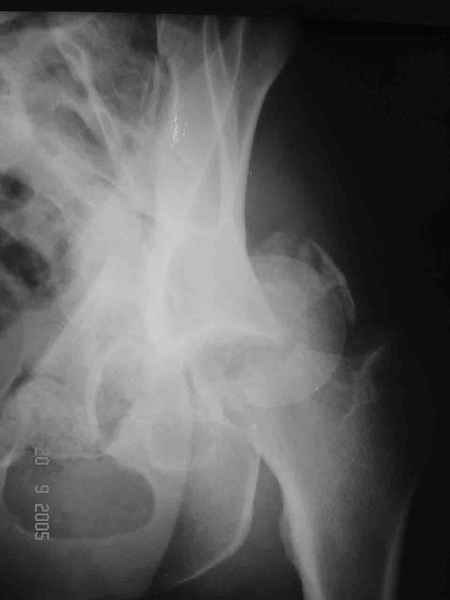

Привет! Вот недавно прооперировали похожий на ваш случай - впадина + шейка (правда у нас впадина поперечный+задний край). После травмы прошло 4 недели. мужчине 46 лет. С такой комбинацией все показания к первичному протезированию. Морально и технически мы к этому уже созрели.Но больной не собрал денег на протез. Выполнили остеосинтез впадины и шейки, прекрасно понимая, что головка вскоре рассосется, мы хотя бы надемся что к этому времени таз срастется, как говорится создали все условия для дальнейшего протезирования (может, и протез в последующем подешевле будет, в смысле, без укрепляющего кольца?). Привет Рункову!

Отправитель: Рунков 27 Сентябрь 2005, 09:57

Привет Алекей! Сделано неплохо, поздравляю, хотя второй винтик можно было бы и подлиннее в шейку загнать! Пара вопроов: доступ такой же? головка была свободной или висела на капсуле?

Согласен, можно было и подлиннее. Доступ такой же - чрезвертельный, только разрез кожи прямой (а не Y, чего то я разницы не ощущаю). Головка была абсолютно свободной (то есть во время остеосинтеза таза лежала в стакане и не мешалась). Шансов, что она прирастет 0,00001%. Хотели даже выбросить, но привинтили как временный биологический протез (читай свободный трансплантат), чтоб на период срастания таза бедро проксимально не ушло (может ортопеды потом спасибо скажут). Ну а у вас первичное протезирование при переломе впадины тоже пока полько в планах?